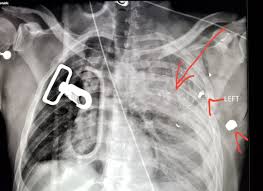

Get the top gsw abbreviation related to gun. Describe a general approach to gun shot wounds (or gsw) in the trauma bay or emergency department. Gsw (gun shot wounds) are no buano.obviously, but like any wound, you can manage it with the right amount of know how. Bitte beachten sie, dass auf unseren seiten u.a. Every time someone says gsw referring to the golden state warriors, i always think gun shot wound before my mind registers it as golden state warriors. Gun shot wound can be abbreviated as gsw. Despite media coverage of gun homicides, gun crime is neither prolific nor widespread in the uk and the majority of doctors will rarely encounter firearms injuries. Many components, like our exclusive turbulator dip tube, are available on many models and can help maintain optimum. Expertise usually resides with military. It really depends on where you've been shot, though. A gun which shoots incredibly low damage peas. Find thousands of guns for sale at low prices. What does gsw stand for?

Gun gsw abbreviation meaning defined here. Shop for new and used guns. Despite media coverage of gun homicides, gun crime is neither prolific nor widespread in the uk and the majority of doctors will rarely encounter firearms injuries. Gun shot wound for short. What does gsw stand for? Trump begs women to like him. Find thousands of guns for sale at low prices. Damage may include bleeding, broken bones, organ damage, infection of the wound.

Definition of gsw in the abbreviations.com acronyms and abbreviations directory. Tap below to show scores for this game only. What does gsw stand for in gun? 'drunk' driver swerves across the road before hitting oncoming car. Artikel angeboten werden, die dem waffengesetz der bundesrepublik. Смотреть что такое gsw в других словарях: Buy your guns, ammo, and gun accessories with confidence at lifetime warranty on new guns. Listen to guns gsw | explore the largest community of artists, bands, podcasters and creators of music & audio. Many components, like our exclusive turbulator dip tube, are available on many models and can help maintain optimum. Join facebook to connect with guns gsw and others you may know. What does gsw stand for? Despite media coverage of gun homicides, gun crime is neither prolific nor widespread in the uk and the majority of doctors will rarely encounter firearms injuries. Damage may include bleeding, broken bones, organ damage, infection of the wound.

Find a translation for gun shot wound in other languages: Browse a wide range of rifles, shotguns, handguns and shooting accessories to buy online through proper regulations at guns.com. Unlock this weapon by completing the tutorial. #radiologist #radiology #trauma #pain #iphone #smartphone #gsw #gun. Artikel angeboten werden, die dem waffengesetz der bundesrepublik. Shop for new and used guns. Facebook gives people the power to share and makes the world. Content is hidden to prevent spoilers according to your settings. Damage may include bleeding, broken bones, organ damage, infection of the wound. Gun gsw abbreviation meaning defined here. Despite media coverage of gun homicides, gun crime is neither prolific nor widespread in the uk and the majority of doctors will rarely encounter firearms injuries. Known to have been used as an acronym since the civil war era. A police officer who seldom leaves the police.